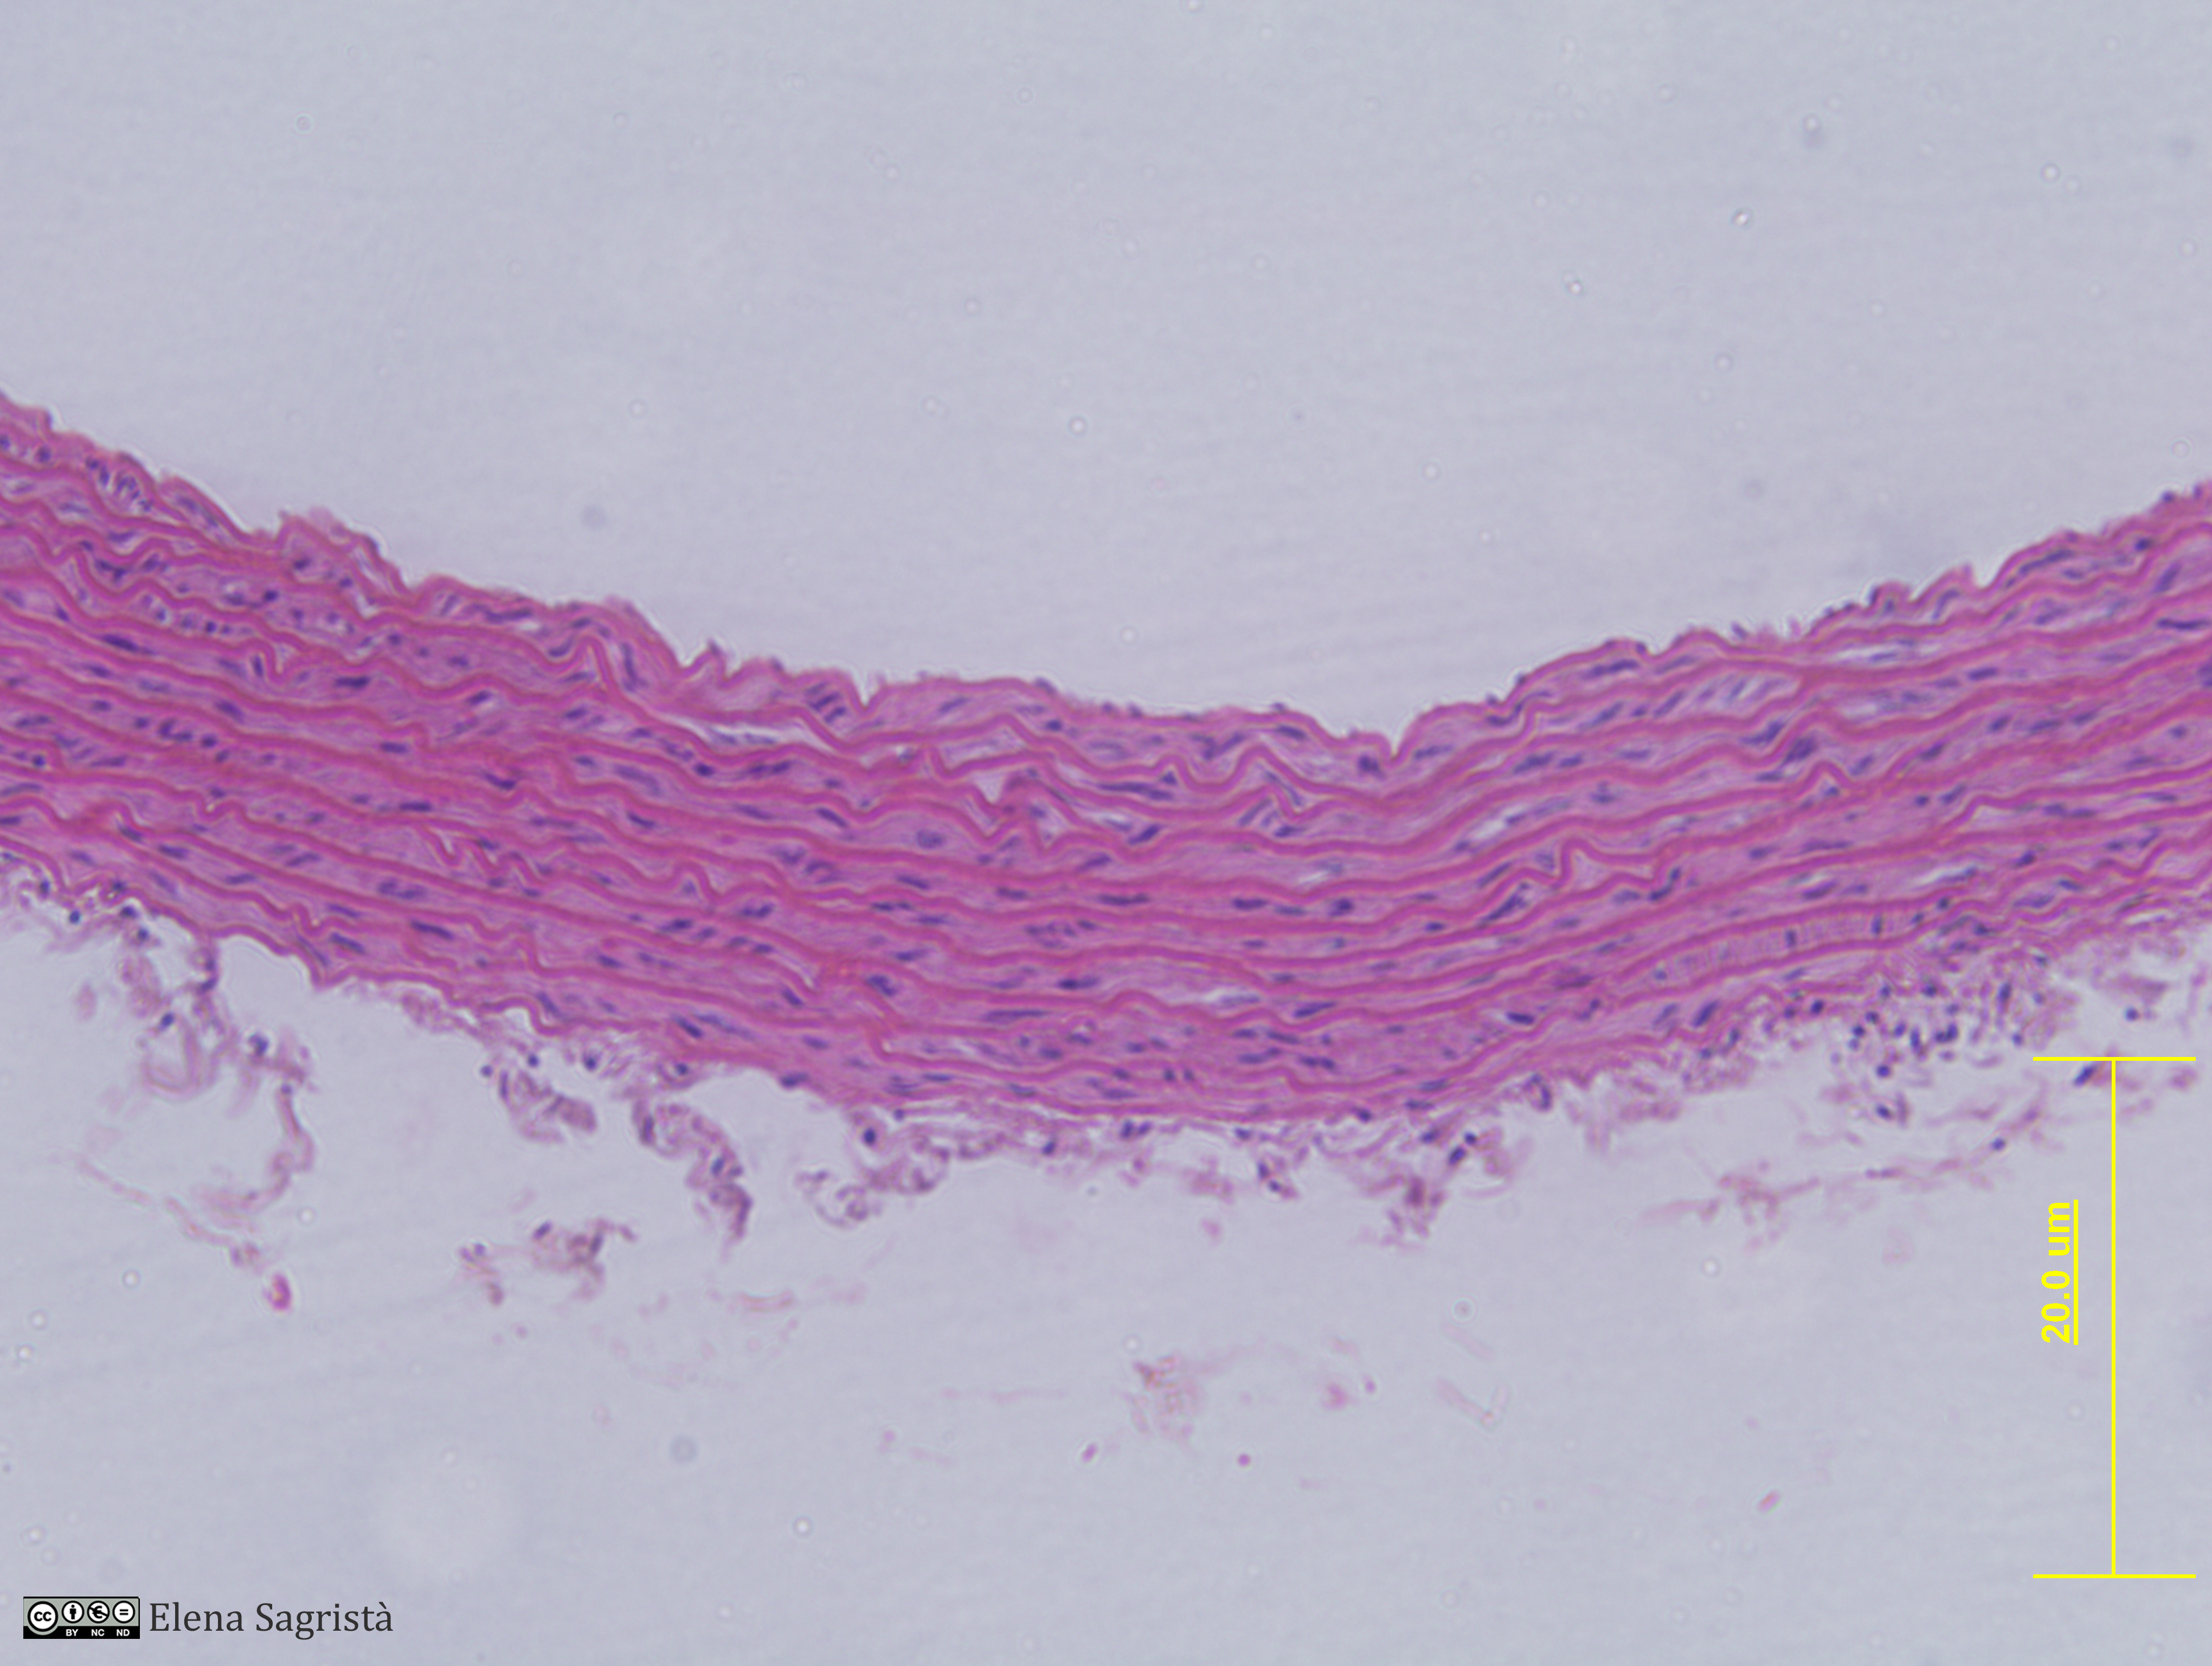

Histologia imatges: 10 Vasos sanguinis i limfàtics

Imatges de preparacions histològiques de Vasos sanguinis i limfàtics. Microscopia òptica.